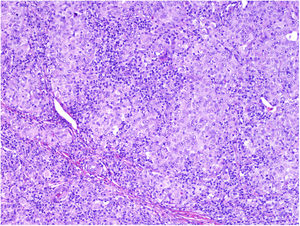

NeurotropismNeurotropism is defined as the presence of melanoma cells either adjacent to nerve sheaths, usually circumferentially (perineural invasion) (Fig. 3), or within a nerve (intraneural invasion) (Fig. 4). It is more commonly seen at the periphery of the tumor. Nerve entrapment due to an expanding tumor should not be regarded as neurotropism. Neurotropism is often observed in desmoplastic melanomas. It can sometimes extend beyond the primary tumor and is therefore associated with a higher risk of local recurrence.36 Neural differentiation in melanomas, generally desmoplastic, is also considered to be a form of neurotropism (Fig. 5).10